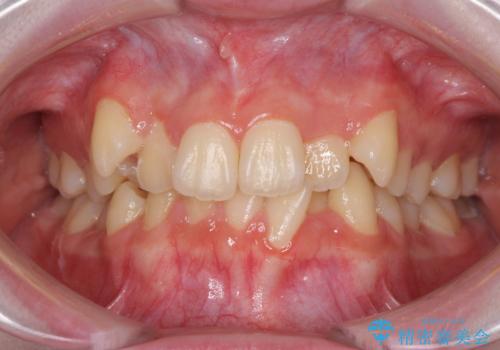

- 上下前歯のデコボコを気にして来院された患者様です。

前歯の叢生は強かったのですが、口元が引っ込んでいる印象であったため、非抜歯にて矯正治療を行うこととしました。